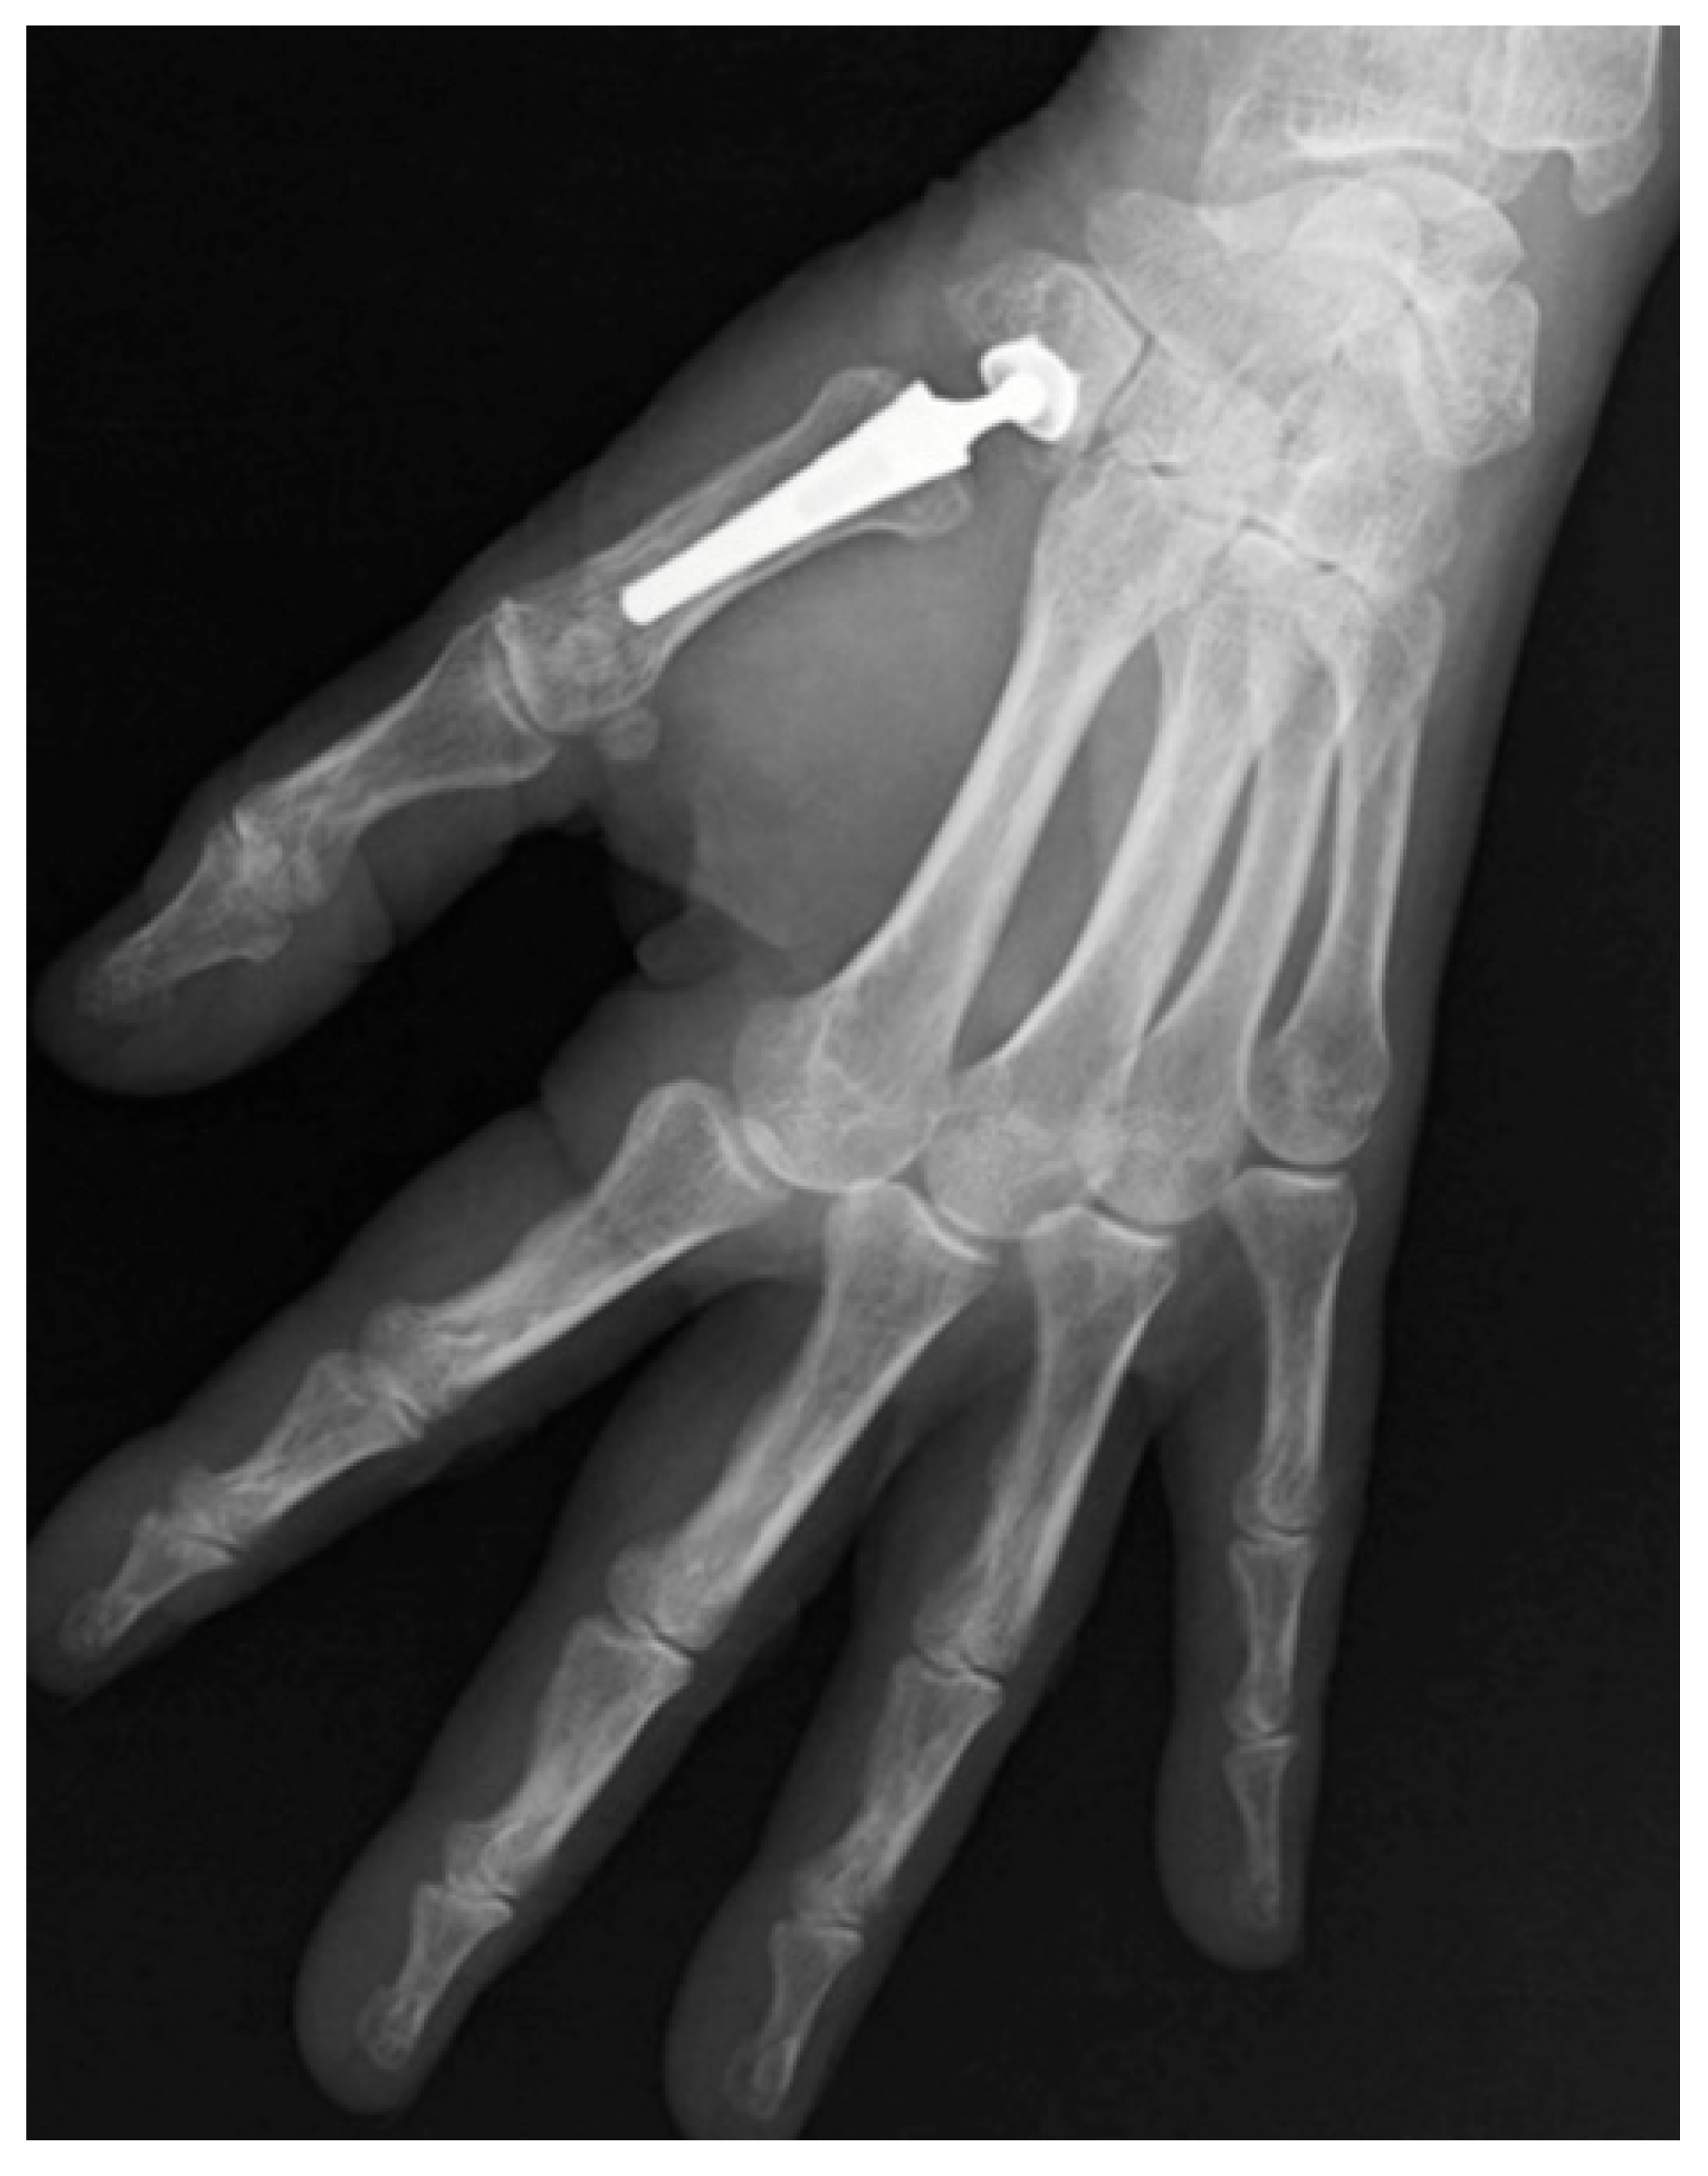

3.3. Type of Prosthesis